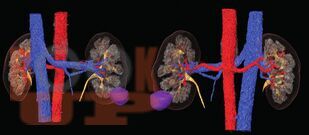

В данном учебном пособии представлены сведения по анатомии и физиологии почек, эпидемиологии, этиологии, патогенезу, клинике, диагностике и современному хирургическому лапароскопическому лечению опухолей почек.